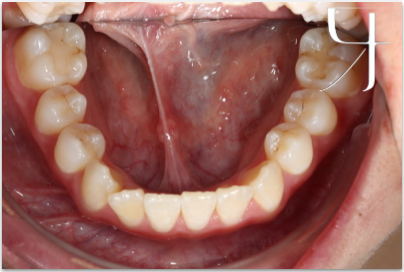

Before

病患和媽媽覺得牙齒排列不整齊看起來很亂,除了有小虎牙之外​,也覺得下巴歪歪的,側面看起來還會覺得下巴比較往前頃,希望能藉由矯正的方式改善。

一般高中生年齡來找陳醫師做矯正的患者為數眾多,醫師會配合臉部外型、頭骨發育等基本面向先做評估,其次再針對牙齒排列與臉部的相對位置等問題進一步評估。下巴歪斜的清況每個人都會有,在不是非常明顯的情況前提下,將牙排列整齊的同時骨頭會稍微被調整一點;現在病患能夠很大方的開懷大笑、給予我們充滿自信的笑容!

此案例病患利用外側陶瓷美觀矯正器矯正治療,在唸書的年紀矯正,雖然忙碌辛苦一點,但甜美的果實總是在一番努力後更加鮮甜;患者與家長十分滿意治療的結果,樂心牙醫診所也為患者開心!